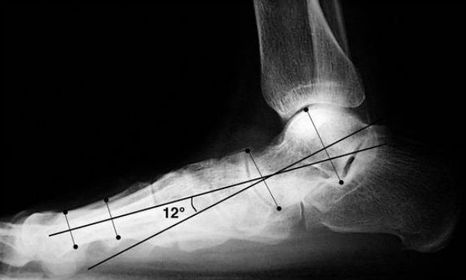

| What is this angle called? What foot type does it indicate? | Talar - 1st MT or Meary's Angle Pes plano-valgus |

| What is this angle called? What foot type does it indicate | Talar - 1st MT or Meary's Angle Pes cavo-varus |